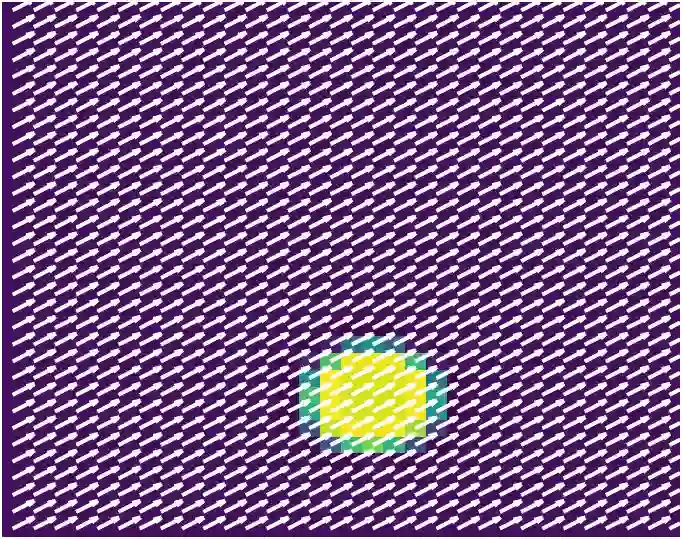

Various imaging modalities allow for time-dependent image reconstructions from measurements where its acquisition also has a time-dependent nature. Magnetic particle imaging (MPI) falls into this class of imaging modalities and it thus also provides a dynamic inverse problem. Without proper consideration of the dynamic behavior, motion artifacts in the reconstruction become an issue. More sophisticated methods need to be developed and applied to the reconstruction of the time-dependent sequences of images. In this context, we investigate the incorporation of motion priors in terms of certain flow-parameter-dependent PDEs in the reconstruction process of time-dependent 3D images in magnetic particle imaging. The present work comprises the method development for a general 3D+time setting for time-dependent linear forward operators, analytical investigation of necessary properties in the MPI forward operator, modeling aspects in dynamic MPI, and extensive numerical experiments on 3D+time imaging including simulated data as well as measurements from a rotation phantom and in-vivo data from a mouse.